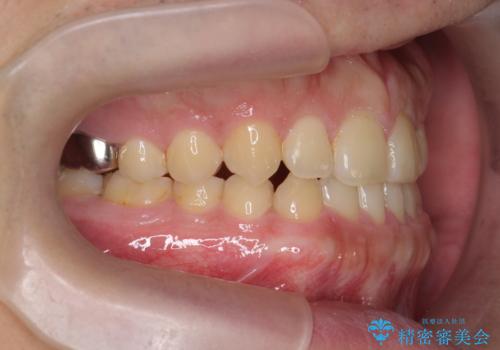

- 前歯の噛み合わせが反対になっていること、前歯の見た目の改善を希望され来院されました。

詳細な矯正検査の結果、顎の歪みが見られたため大きく歯を動かす治療ではなく前歯を主に並べることで前歯の前後関係を改善していきます。

前歯を主に動かす部分矯正であることからマウスピース矯正インビザラインによる治療を計画します。